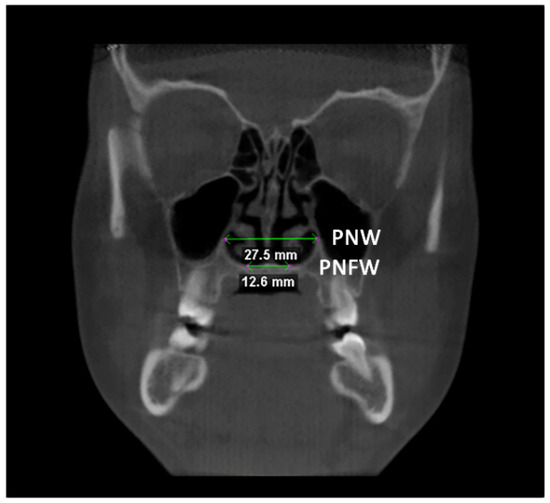

Afterward, the transverse dimension of the Apertura Piriformis was measured in the anterior and posterior regions. In the coronal plane passing through the cephalometric point N, the linear measurements of anterior nasal width (ANW) and anterior nasal floor width (ANFW) were performed (Figure 3, Table 1). Similarly, in the coronal plane passing through the upper margin of the mesial aspect of the Sella Turcica, the linear measurements of the posterior nasal width (PNW) and posterior nasal floor width (PNFW) were performed (Figure 4, Table 1). The entire procedure for skeletal measurements was performed by using the Dolphin 3D software (Dolphin Imaging, version 11.0, Chatsworth, CA, USA).

Figure 4.

Linear measurements of the posterior nasal width (PNW) and the posterior nasal floor width (PNFW) in the coronal plane.

In both TB and BB groups, there was a statistically significant expansion of the Apertura piriformis (ANW and ANFW) between T0 and T1 (p < 0.05), instead no differences were found between T1 and T2 (p > 0.05), thus maintaining the post-retention changes (Table 3). The expansion of the Apertura piriformis was significantly greater in the BB group compared to the TB group (TB) (p < 0.05) at each time point. The same findings were recorded for the PNW and PNFW measurements (Table 4).

4.1. Post-Retention Transverse Changes

Concerning skeletal measurements, the BB group showed a greater skeletal expansion compared to the TB group, which was consistent with previous findings [8]. The TB group showed a greater expansion of the pyriform aperture width compared to the posterior region confirming the wedge-shaped opening of the suture [4]; instead, BB groups showed a more parallel sutural opening [21]. Furthermore, both groups showed a cranio-caudal pattern of expansion (T0/T1 TB: ANW = 1.12 mm, ANFW = 1.61 mm; T0/T1 BB: ANW = 2.01 mm, ANFW = 2.66 mm), confirming the “V” shape opening of the mid-palatal suture [26]. It should be mentioned that subjects in the BB group were slightly older than those included in the TB group (<1 year); thus, they could present an advanced maturational stage of the mid-palatal suture that would have increased the skeletal resistances compared to TB group [27].